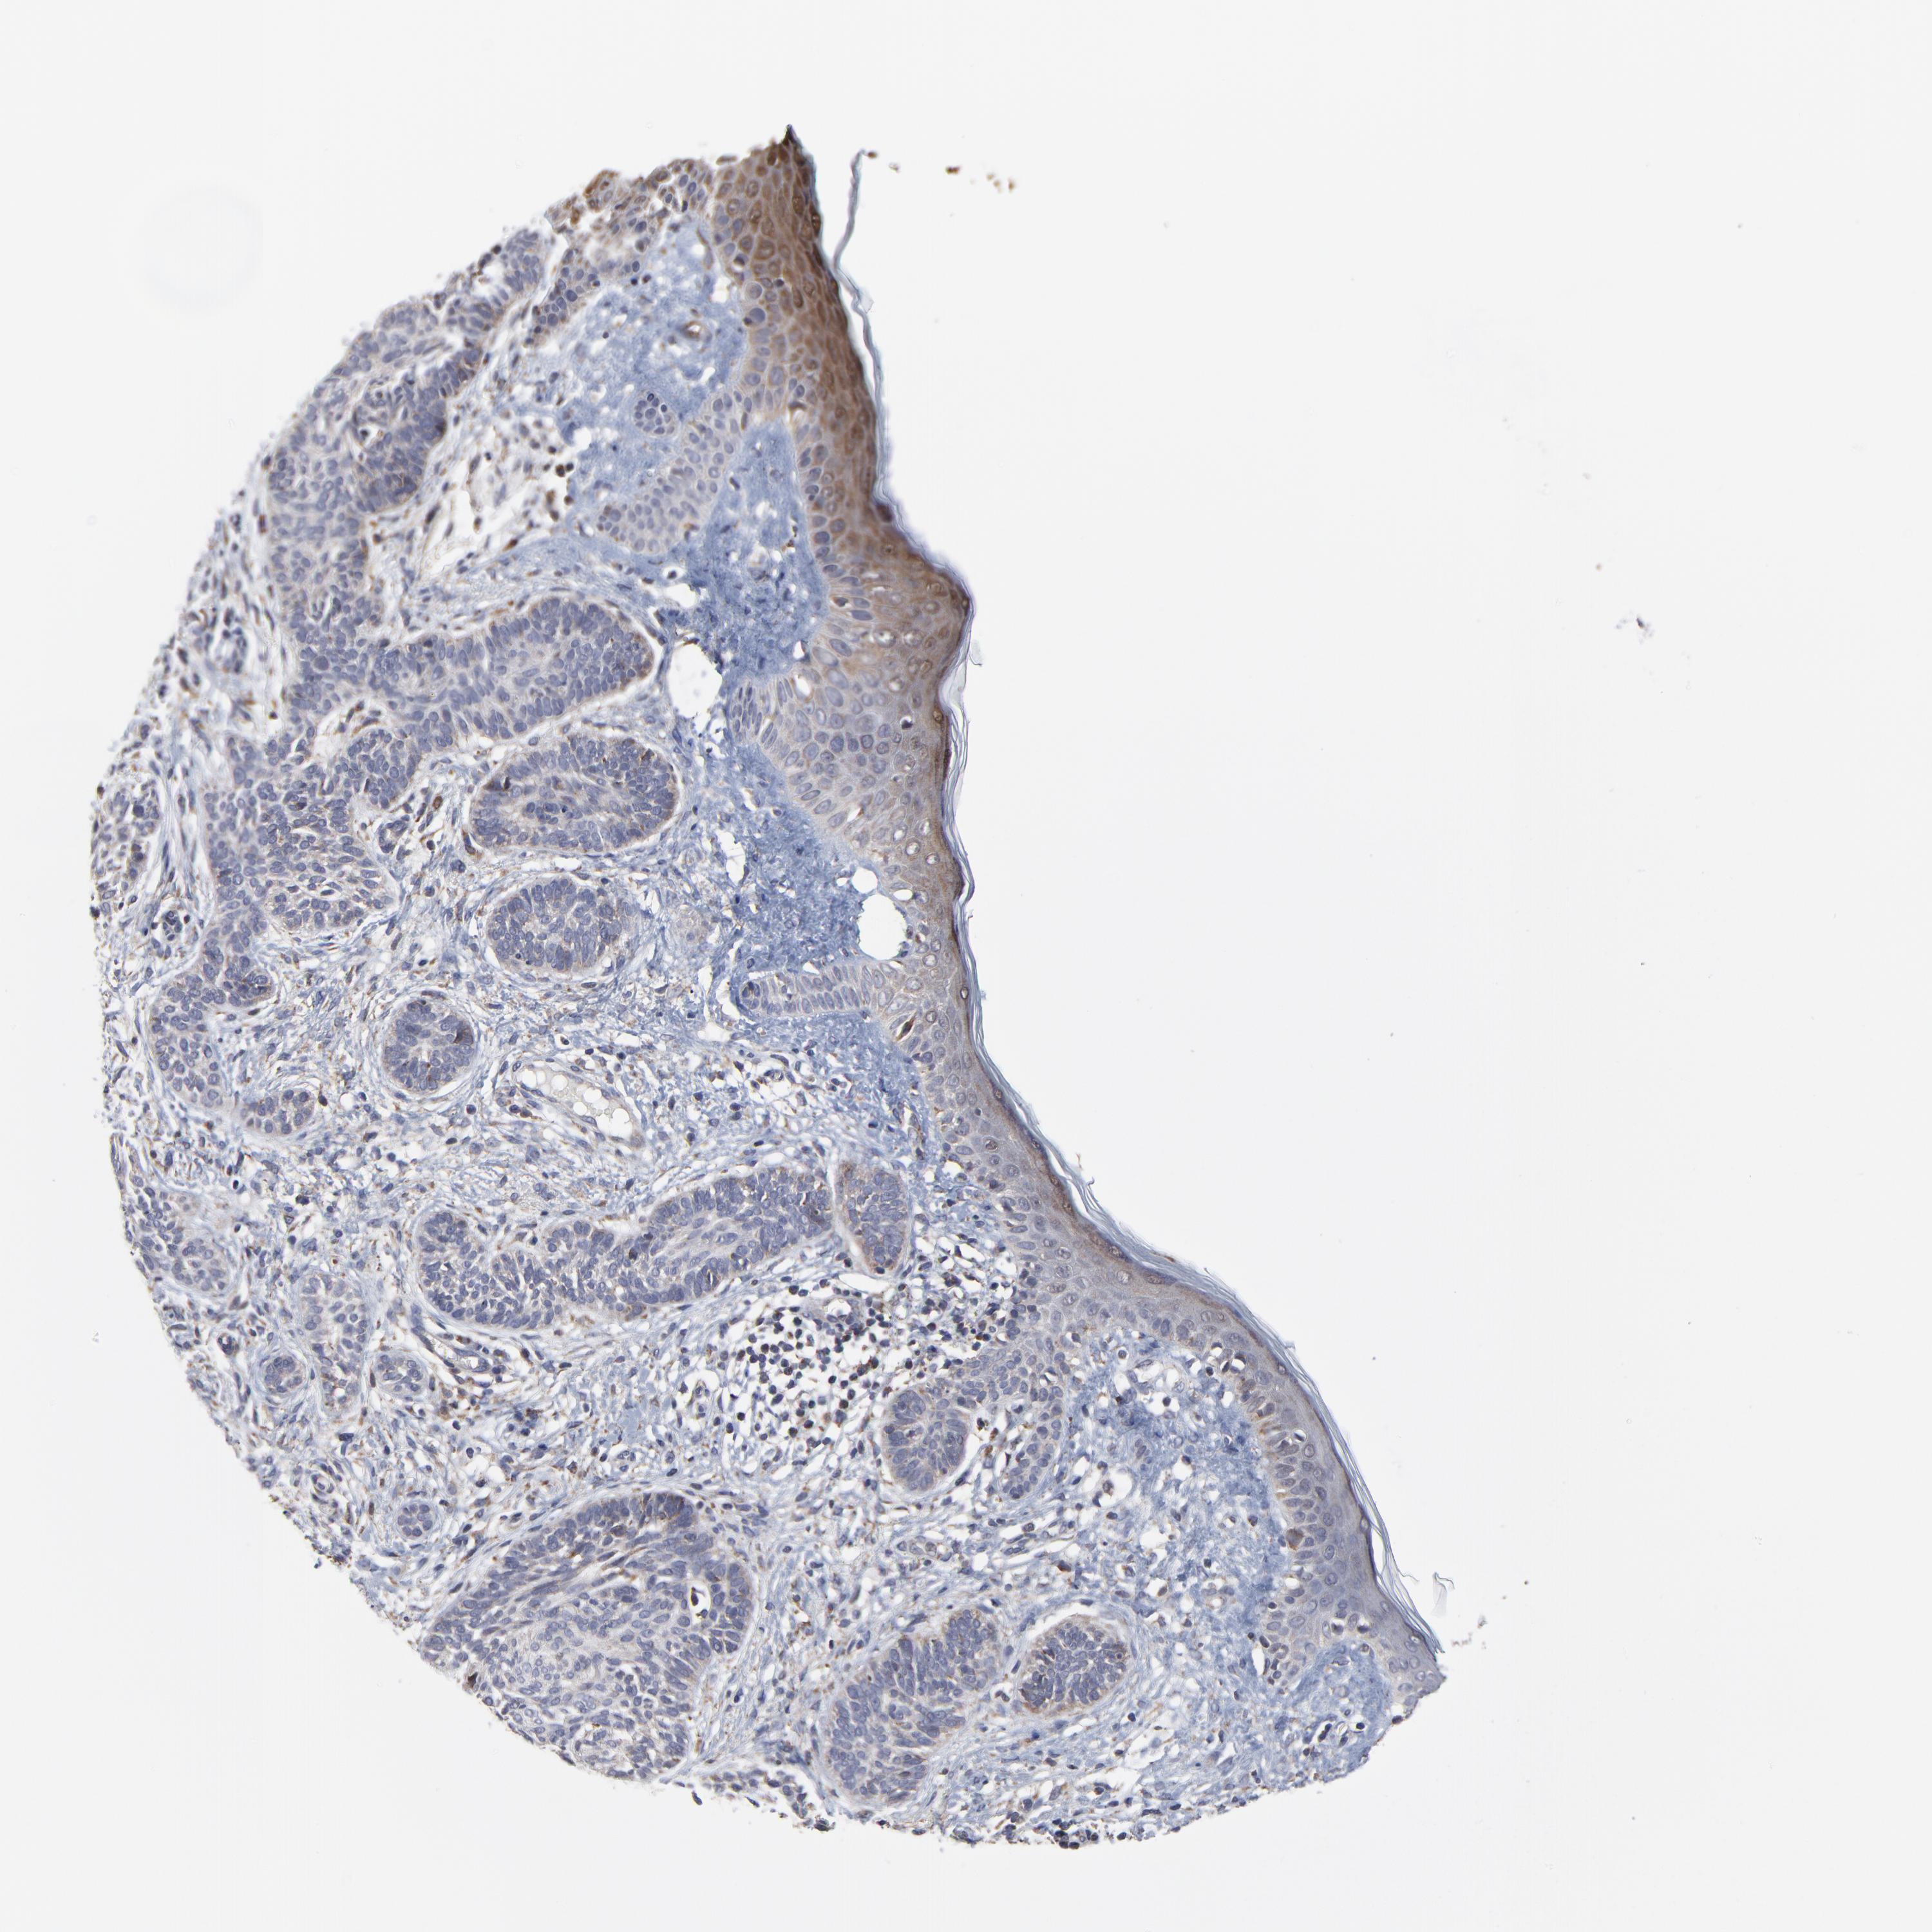

SKIN CANCER - Protein expressioni

A mouse-over function shows sample information and annotation data. Click on an image to view it in a full screen mode. Samples can be filtered based on level of antibody staining by selecting one or several of the following categories: high, medium, low and not detected. The assay and annotation is described here.

Antibody stainingi

Antibody staining in the annotated cell types in the current human tissue is reported as not detected, low, medium, or high, based on conventional immunohistochemistry profiling in selected tissues. This score is based on the combination of the staining intensity and fraction of stained cells.

Each image is clickable and will lead to virtual microscopy that enables deeper exploration of all samples and also displays staining intensity scores, fraction scores and subcellular localization as well as patient and tissue information for each sample.

Antibody HPA003251

Staining

High

Medium

Low

Not detected

Intensity

Strong

Moderate

Weak

Negative

Quantity

>75%

75%-25%

<25%

None

Location

Nuclear

Cytoplasmic/membranous

Cytoplasmic/membranous,nuclear

Squamous cell carcinoma, NOS

Basal cell carcinoma